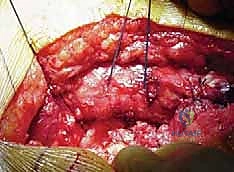

الخطوة الأولى: الشق الجراحي والوصول للمفصل

يقوم الدكتور هطيف بعمل شق جراحي دقيق (غالباً في الجزء الجانبي أو الخلفي من الورك)، مع الحرص الشديد على الحفاظ على العضلات والأوتار المحيطة قدر الإمكان، وهو ما يُعرف بتقنيات الحفاظ على الأنسجة، مما يسرع من عملية التعافي.

الخطوة الثانية: استئصال العظم التالف

يتم خلع المفصل، ثم يُقص رأس عظمة الفخذ التالف باستخدام منشار جراحي دقيق. بعد ذلك، يتم تنظيف التجويف الحُقي (في الحوض) من الغضاريف المتآكلة باستخدام أدوات كروية خاصة لتهيئته لاستقبال الكوب الصناعي.